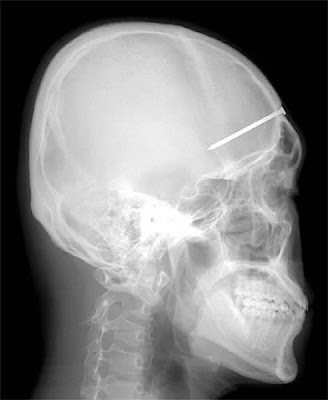

The Most Bizarre X-Rays

A dentist found the source of the toothache Patrick Lawler was complaining about on the roof of his mouth: a four-inch (10-centimeter) nail the construction worker had unknowingly embedded in his skull six days earlier.

The 5-centimeter nail shown in this X-ray was found after a man came to a Seoul, South Korea, hospital complaining of a severe headache. After examining and interviewing the man, doctors speculated that the nail had been the result of an accident four years before his visit, but that the man did not know the nail was lodged in his head.